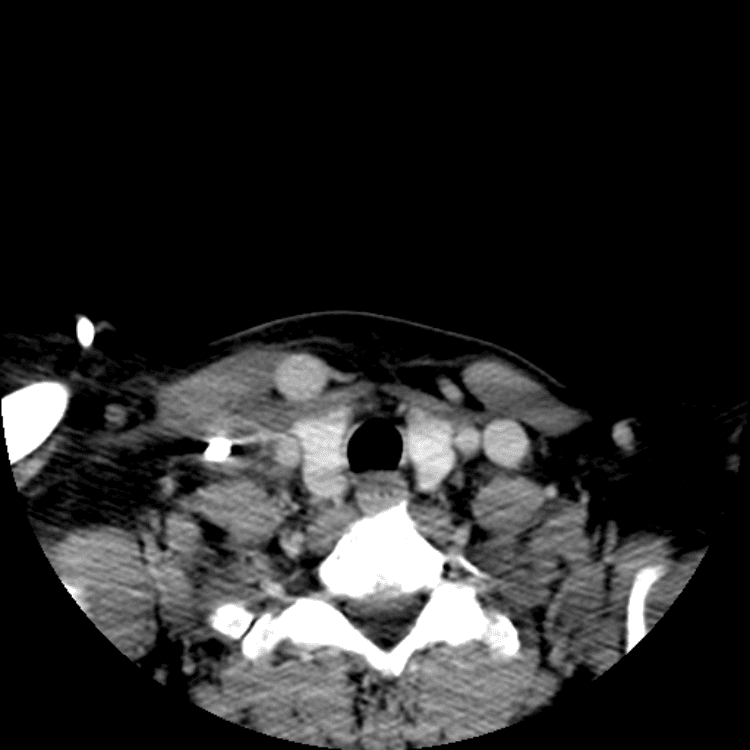

Head and Neck

Practice

Simulates call by including subtle or difficult cases and some normals.

27 cases